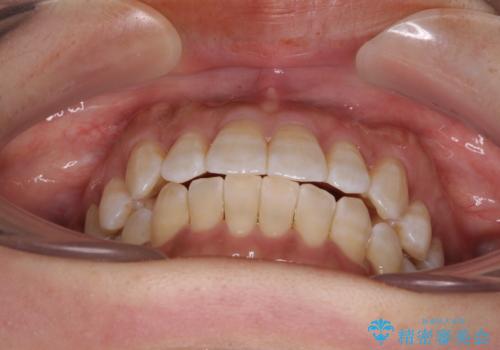

気になる八重歯 ワイヤー装置での非抜歯矯正

- 上顎の八重歯と全体的なデコボコを気にして来院された患者様です。

口元の突出感はなかったため非抜歯矯正での対応となりますが、八重歯を改善する際に上顎前歯が前突する可能性があったため、上顎臼歯部にアンカースクリューを使用して、歯列が前方に転位しないようにすることとしました。

ワイヤー矯正でもインビザラインでも対応可能でしたが、上顎歯列が前方位であるときには、ワイヤー矯正の方がより良い仕上がりとなる可能性が高いため、ワイヤー矯正をおすすめいたしました。